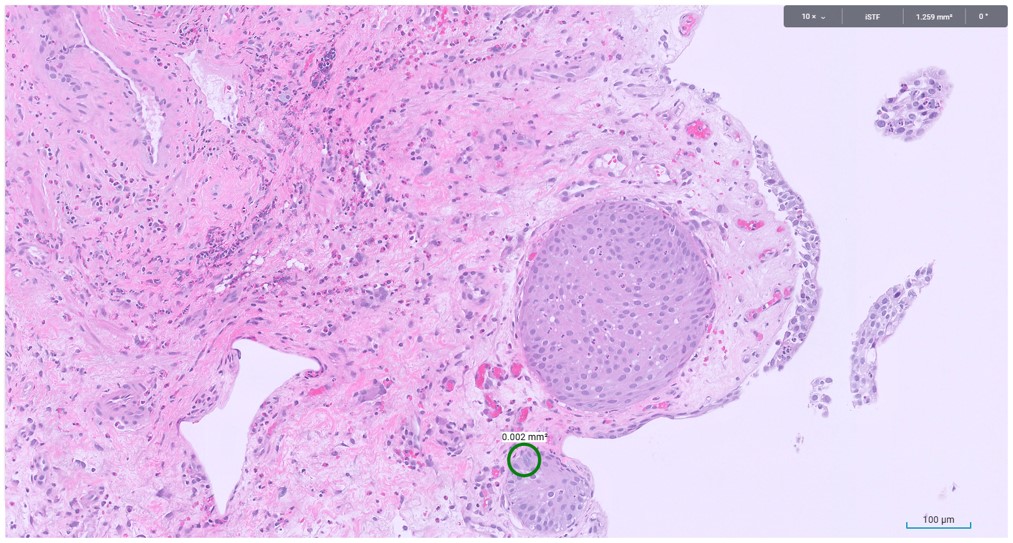

Microscopic image possibly detecting cancerous areas in human tissue